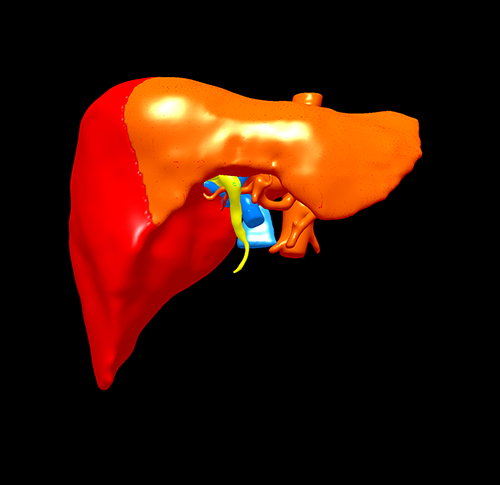

IV型胆管癌---胆管癌根治(左半肝+尾状叶切除)